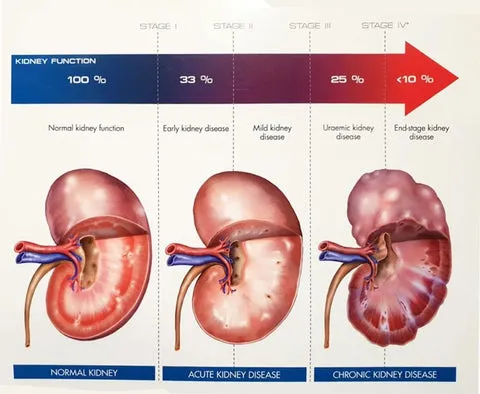

This is what a Healthy Kidney looks like:

This is what a Damaged Kidney looks like

Comparison between Healthy and Damaged Kidneys

A healthy kidney efficiently filters waste and fluids, maintains electrolyte balance, regulates blood pressure, produces beneficial hormones, preserves bone health, and enhances blood circulation. In contrast, a damaged kidney experiences reduced function, leading to waste accumulation, electrolyte imbalance, challenging blood pressure control, hindered hormone secretion, weakened bones, and overall health risks. Early monitoring and management of kidney health are crucial to prevent further damage.

How to Determine the Stages of Kidney Disease

Stage 1: Kidney Health (Stage 1): GFR is normal, but there may be other kidney issues or risk factors present.

Stage 2: Mild Kidney Damage (Stage 2): GFR slightly declines but remains within the normal range, often accompanied by other kidney issues.

Stage 3: Moderate Kidney Damage (Stage 3): GFR further decreases, possibly between 30-59 mL/min/1.73m². This stage may show mild symptoms like fatigue and swelling.

Stage 4: Moderate to Severe Kidney Damage (Stage 4): GFR continues to decline, potentially between 15-29 mL/min/1.73m². More noticeable symptoms might occur, such as anemia and skeletal problems.

Stage 5: Kidney Failure (Stage 5): GFR is very low, below 15 mL/min/1.73m². This is the most severe stage, requiring kidney replacement therapies like dialysis or kidney transplantation.

If your kidneys are already in Stage 5, kidney patches can only alleviate its complications rather than provide a curative effect. For stages above Stage 4, kidney patches can be used to intervene artificially and aid in the recovery of kidney function.